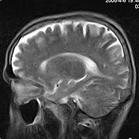

2、MR表現:

①最常見於松果體區,也常見於鞍上,可同時或單獨存在。

②T1加權為略低信號或等信號,T2加權常呈等信號或高信號。

③增強後;呈明顯均勻一致強化,並能發現沿腦脊液或室管膜轉移的病灶。

4.MRI 檢查:MRI 對顯示鞍上小的生殖細胞瘤(直徑<1cm)或脊髓轉移灶十分清楚;顯示松果體區生殖細胞瘤常為圓形、橢圓形或不規則形,多數T1為等或稍低信號,T2 為稍高信號,少數亦可為等信號;注藥後均勻一致的強化,邊界清楚,有時少數僅呈中度或不均勻強化。有報告20%~58%的生殖細胞瘤有小的囊變,這些囊變由於蛋白性液體或壞死液化所致,通常極小,有時在瘤內有小出血灶,在T1 像為高信號;松果體區者可侵犯中腦和丘腦,在T2 像上有周邊模糊高信號影。MRI 對腫瘤的種植或播散顯示全面,除了T1及T2像的多發病灶顯示清晰,而注藥後病變明顯強化。底節生殖細胞瘤也是T1等或低信號,而T2稍高信號,注藥後可均勻強化,有的顯示同側皮層有萎縮現象。